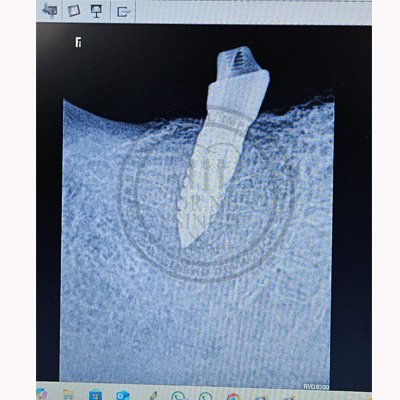

Case – 11 Baleram